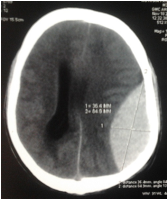

Delayed EDH after assault:

31 year male was assaulted with wooden stick. 24 hours later he developed altered sensorium. He was initially managed in some primary center and 36 hours later was referred to us. On evaluation he was found to be comatose [ GCS=7] with right sided weakness. CT head showed large left parietal EDH with overlying compound depressed fracture. He was taken up for emergency evacuation. He became conscious in 4 hours after surgery. Post op patient was kept on endotracheal tube for 18 hours and then was successfully extubated. His weakness on right side gradually started improving.

Even though there was a delay of almost 36 hours after patient worsened in the primary center; urgent evacuation on arrival resulted in a satisfactory outcome.